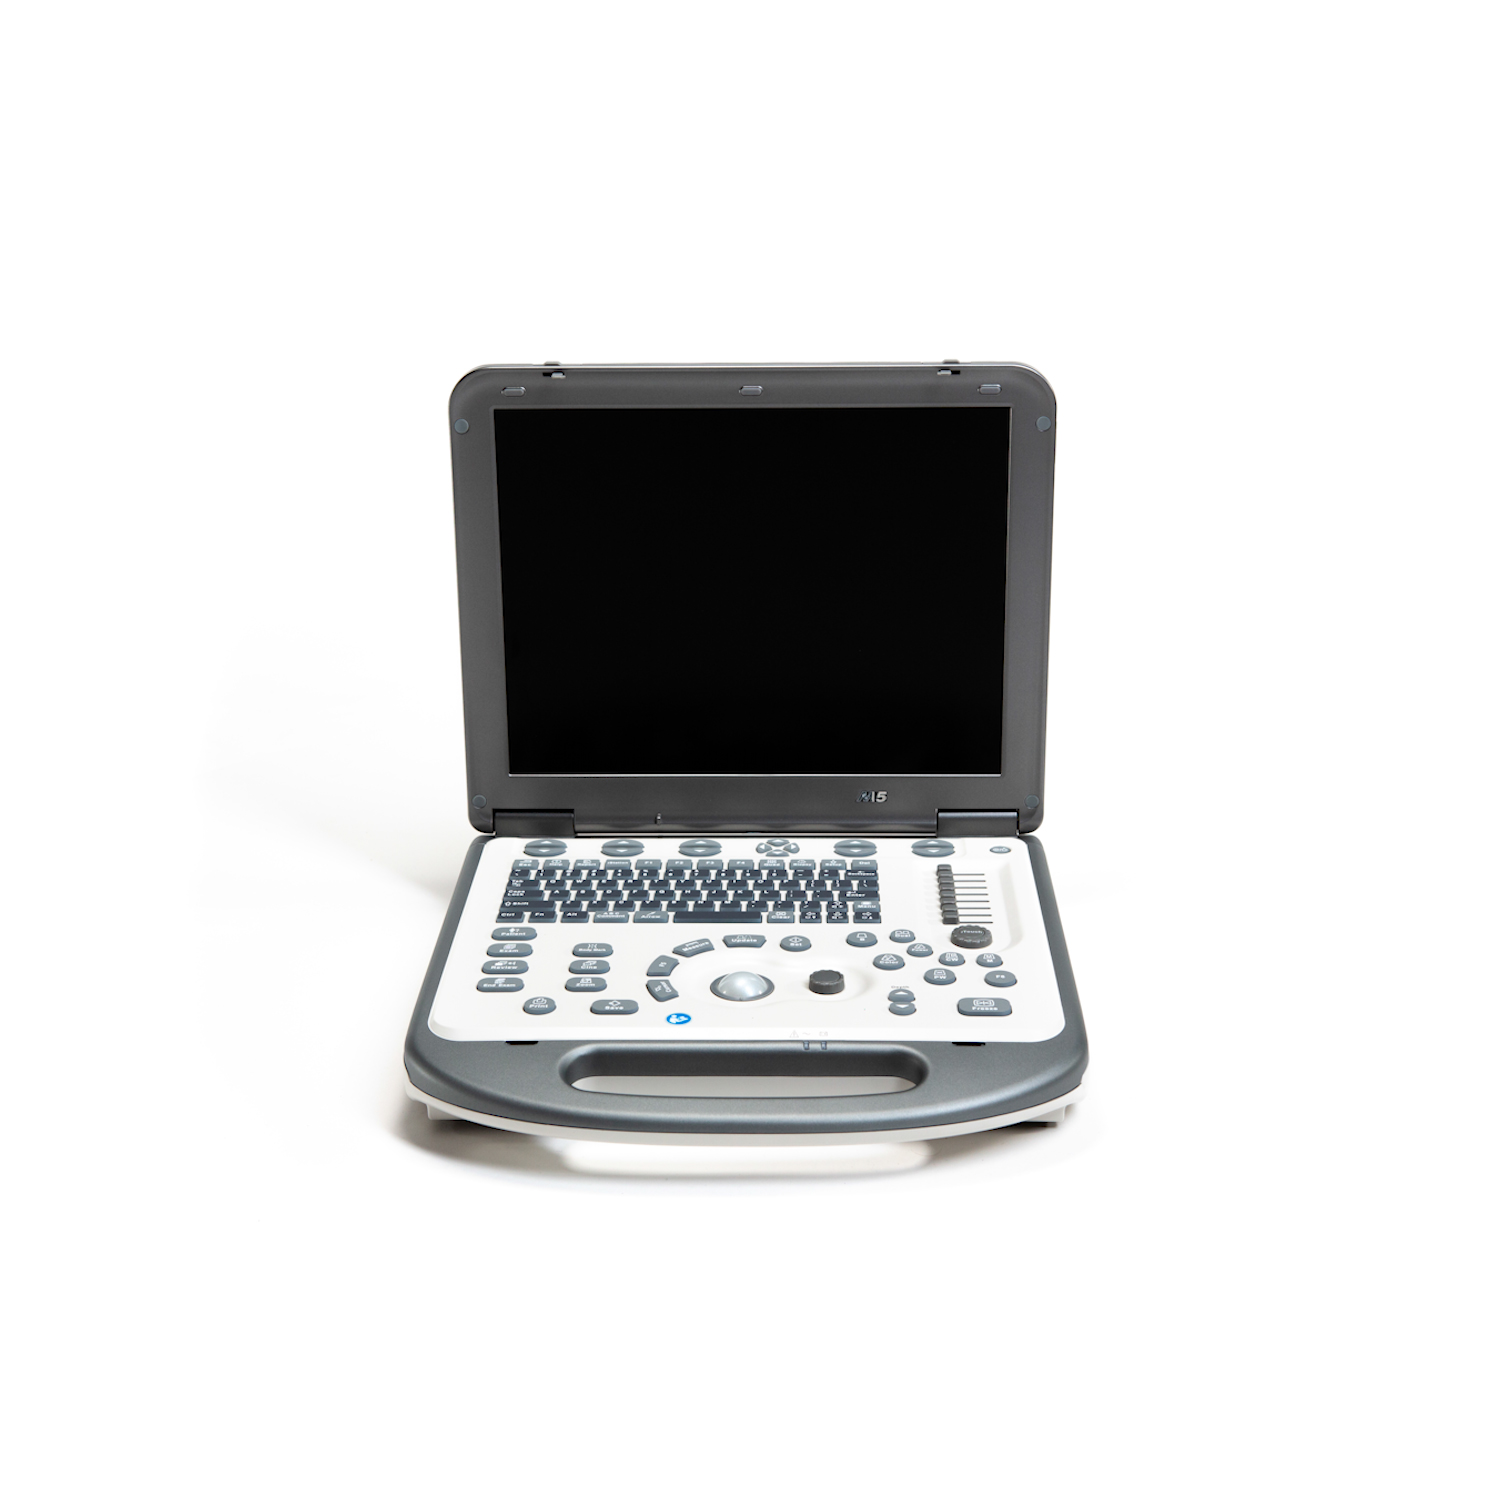

УЗИ аппараты

УЗИ аппараты

УЗИ аппараты

УЗИ аппараты

УЗИ аппараты

УЗИ аппараты

УЗИ аппараты

УЗИ аппараты

УЗИ аппараты

УЗИ аппараты

УЗИ аппараты

УЗИ аппараты

УЗИ аппараты

УЗИ аппараты